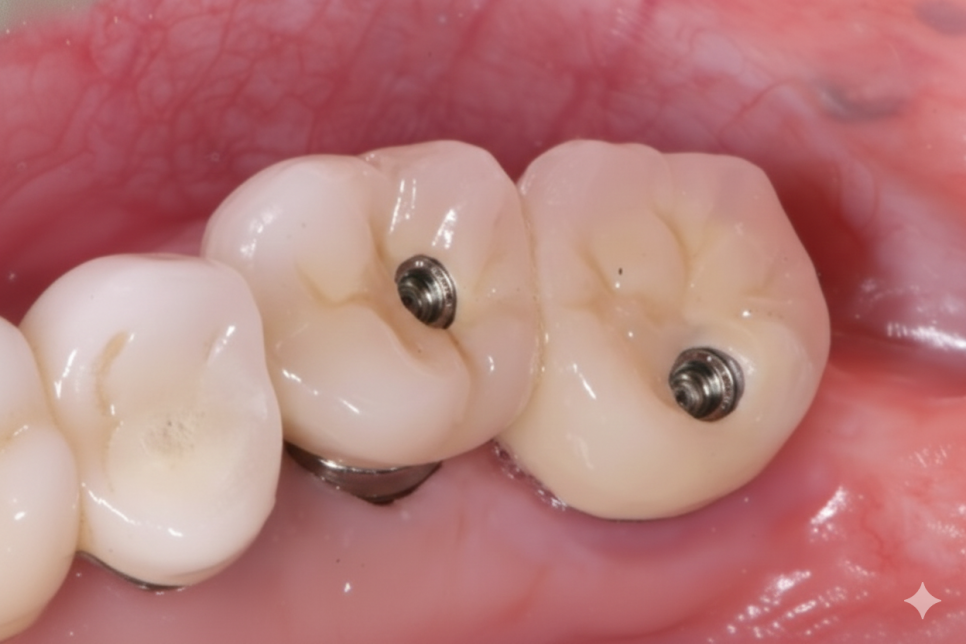

튼튼한 지르코니아 & SCRP로 교체

고덕 치과, 임플란트가 흔들려요. 뽑아야 할까 봐 고민이라면?

제거해 보니 다행히 내부 기둥은

멀쩡해 그대로 사용했습니다.

240614

덕분에 기둥을 새로 제작하지 않아,

환자분의 비용 부담은 줄일 수 있었어요.

도자기는 쓰다보면 겉의 도자기가 깨지는

경우가 종종 있어

더 튼튼하고 잘 깨지지 않는

'지르코니아'로 새로 제작해 드렸습니다.

이번에는 구멍이 없는 방식이 아니라,

씹는 면에 아주 작은 나사 구멍을 만들어는

'SCRP 방식'으로 변경했습니다.

240626

혹시라도 나중에 또 나사가 풀려도,

이제는 보철물을 뜯어내며

고생하실 필요가 없습니다.

구멍을 메워둔 재료만 살짝 걷어내고

드라이버로 1분 만에 조이면 끝나거든요.

꽤 간단하죠?